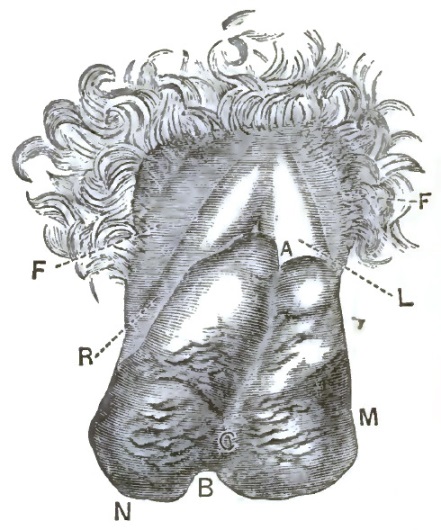

| 1. | THE CLASSICAL REPRESENTATION OF THE PELVIC ORGANS |

| 2. | THE CORRECT REPRESENTATION OF THE PELVIC ORGANS |

| 3. | FIRST DEGREE OF PROLAPSE OF THE POST-PARTUM UTERUS |

| 4. | SHOWING EXTREME DESCENT OF THE UTERUS AND OF THE PELVIC FLOOR, AND THE HERNIAL CHARACTER OF THE LESION |

| 5. | DESCENT OF THE VIRGIN UTERUS INTO THE VAGINAL CANAL, SHOWING THE REDUPLICATED VAGINAL WALLS |

| 6. | DESCENT OF THE UTERUS, SHOWING EXCESSIVE CIRCULAR ENLARGEMENT OF THE LACERATED CERVIX, CONSEQUENT UPON REDUPLICATION OF THE VAGINAL WALLS AND OUT-ROLLING OF INTRACERVICAL TISSUES |

| 15. | EXTREME RETROFLEXION, WITH HYPERTROPHY OF THE CORPUS |

| 16. | COMMENCING REPOSITION OF THE RETROVERTED OR RETROFLEXED UTERUS BY CONJOINED MANIPULATION |

| 17. | COMPLETED REPOSITION OF THE RETROVERTED OR RETROFLEXED UTERUS BY CONJOINED MANIPULATION |

| 18. | SHOWING THE PELVIC ORGANS SUSTAINED BY THE EMMET PESSARY AFTER REPOSITION OF THE PROLAPSED, RETROVERTED, OR RETROFLEXED UTERUS |